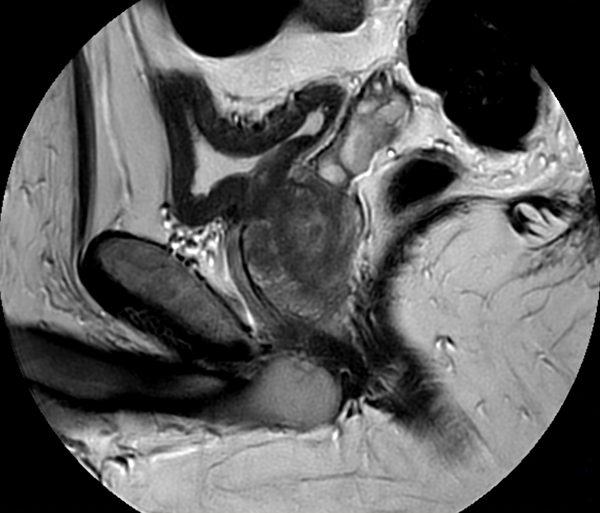

Motion-free Prostate imaging

Used Solution